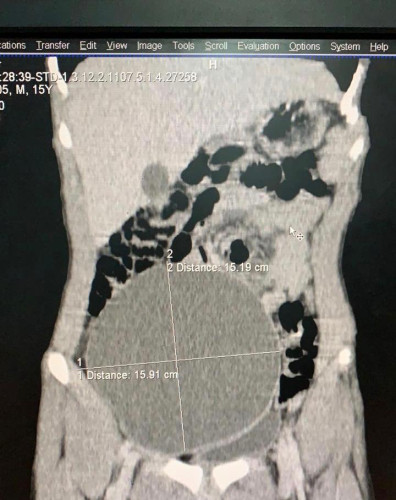

تمكن بفضل الله الفريق الطبي بقسم المسالك البولية وقسم الجراحة العامة بمستشفى عفيف العام من إنهاء معاناة مريض من تورم في الجانب الأيمن من البطن وكذلك تورم في كيس الصفن وبعمل الفحوصات تبين وجود قيلة مائية في خصية معلقة في منطقة الأرب الأيمن وممتدة للحوض والبطن حتى مستوى الفقرة القطنية الثالثة بحجم (٢٦سم *١٦سم *١٣.٥سم )وضاغطة على الأمعاء والحالبين مسببة تضخم في الكليتين وقد تم إجراء عملية إستئصال للكيس وتنزيل الخصية لكيس الصفن وإصلاح الفتق الأربيالأيمن بدون أي مضاعفات ولله الحمد ، واضاف” العمري ” بأن مثل هذا التصفن ضمن 100 حاله عالمياً ومن النادر حدوثها .